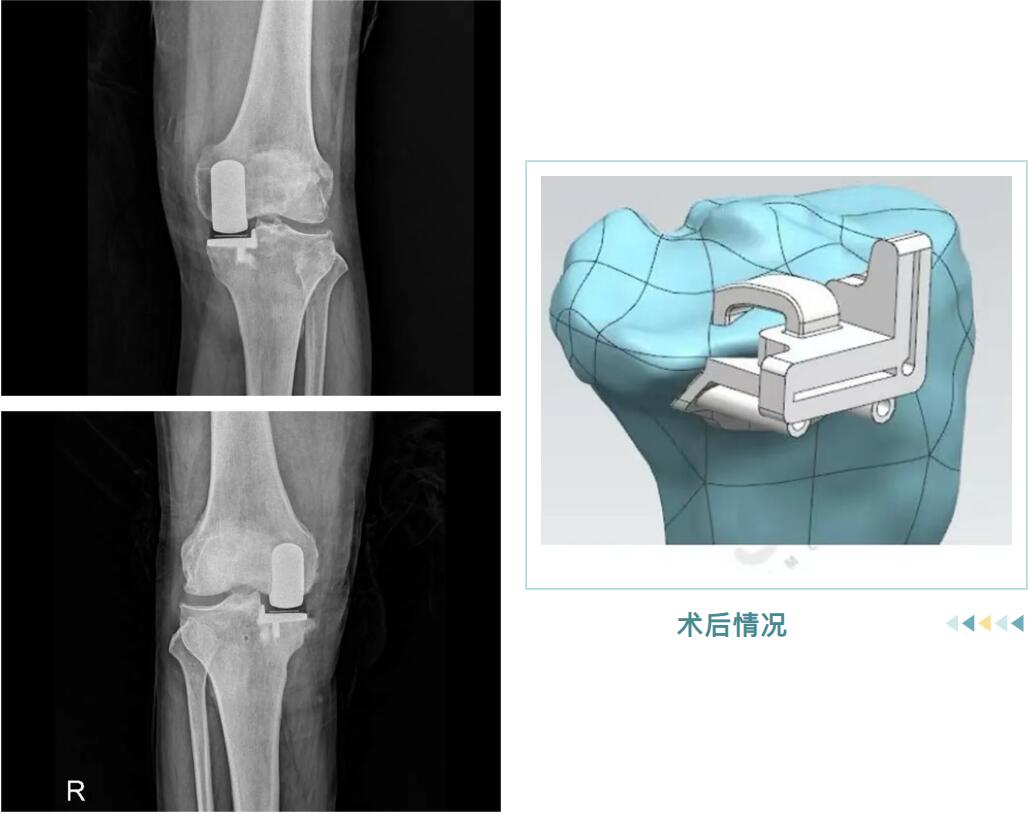

從精準(zhǔn)的3D術(shù)前規(guī)劃,到羅院長(zhǎng)團(tuán)隊(duì)嫻熟的手術(shù)操作,再到術(shù)后個(gè)性化的康復(fù)指導(dǎo),整個(gè)過(guò)程高效而順利。很快,邵阿伯的“羅圈腿”變直了,術(shù)后他輕松站起,行走時(shí)仿佛時(shí)光倒流十年。

術(shù)后情況

什么是膝關(guān)節(jié)內(nèi)側(cè)單髁置換術(shù)?

它并非換掉整個(gè)膝蓋,而是用仿生“小墊片”精準(zhǔn)替換掉內(nèi)側(cè)磨損的軟骨面。手術(shù)僅處理病變部分,保留了您前后交叉韌帶和健康的軟骨,最大程度維持了膝關(guān)節(jié)原有的自然運(yùn)動(dòng)感和穩(wěn)定性。